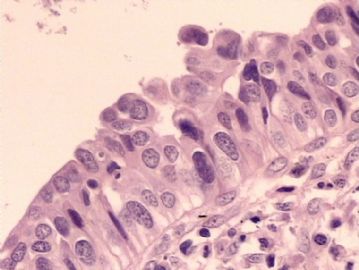

腺鳞癌?

姓    名: ××× 性别:   年龄:  39岁

标本名称:  宫颈活检

简要病史:  同房出血3次,tct HSIL

考虑:原位腺癌,小灶性区域有鳞状上皮向间质内浸润,考虑有鳞状细胞癌结构。